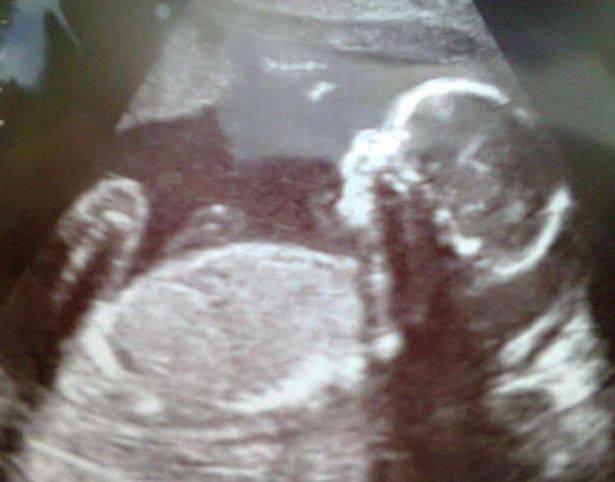

Amy ha scoperto che c’era qualcosa che non andava quando Ollie aveva 20 settimane. Durante un’ecografia di controllo si è scoperto che c’era del tessuto inaspettato che stava crescendo sul suo volto.

Esami più approfonditi hanno mostrato che si trattava di un encefalocele, un difetto per cui il cervello si sviluppa in un buco dentro il cranio.

Nel caso di Ollie questo si è formato sul naso, dividendolo in due.